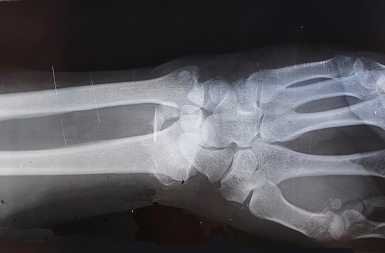

Hand & Wrist

We treat common hand and wrist conditions such as carpal tunnel syndrome, trigger finger and arthritis.